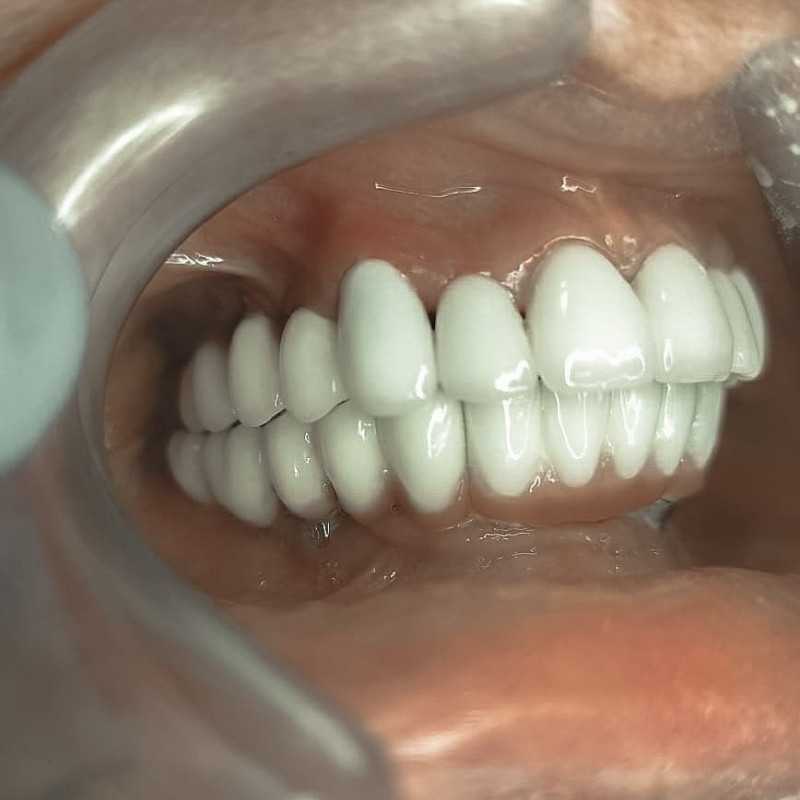

Жалобы: на отсутствие зубов, неудовлетворительную эстетику зубных рядов, невозможность жевать, подвижность зубов. Что сделано: удаление зубов на в/ч и н/ч, установка имплантатов Bredent Sky (верхняя челюсть 6 импл, нижняя 4 импл) и одномоментное протезирование акриловыми протезами с опорой на имплантаты по протоколу Fast & Fixed (зубы за один день). Через 10 месяцев проведена работа по замене протезов на постоянные металлокерамические. Что получил пациент: красивую улыбку, возможность нормально питаться с первого дня после операции.

Жалобы: на отсутствие зубов, неудовлетворительную эстетику зубных рядов, невозможность жевать, снижение высоты прикуса. Что сделано: удаление зубов на в/ч и н/ч, установка имплантатов Bredent Sky и одномоментное протезирование акриловыми протезами с опорой на имплантаты по протоколу Fast & Fixed (зубы за один день). Через 8 месяцев проведена работа по замене протезов на постоянные металлокерамические. Что получил пациент: красивые и ровные зубные ряды, возможность нормально питаться с первого дня после операции, поднята высота прикуса, теперь не стесняется улыбаться.